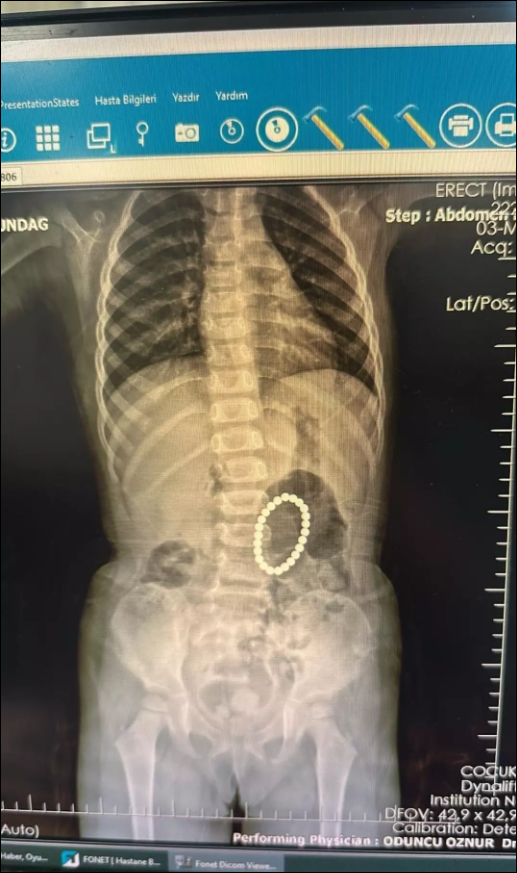

küçük kızın bağırsağından çıkanlar şaşkına çevirdi.